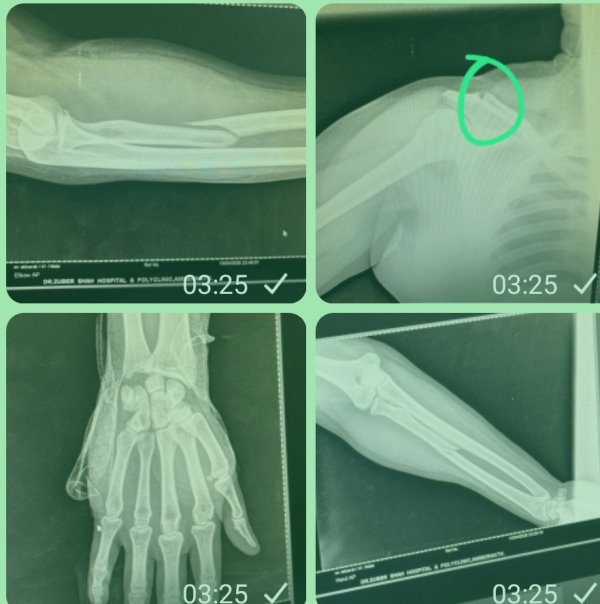

मिली जानकारी के मुताबिक, शॉप को लेकर चल रही पुरानी रंजिश के चलते आज शाम करीब 7 से 8 बजे के बीच 15 से 20 अज्ञात हमलावरों ने सुनियोजित साजिश के तहत अकबर अली शेख पर कोयता, लोहे की रॉड और अन्य धारदार हथियारों से हमला कर दिया।

हमला इतना खतरनाक था कि इलाके में दहशत का माहौल बन गया। हालांकि, इस जानलेवा हमले में अकबर अली शेख बाल-बाल बच गए। फिलहाल उन्हें अंबर अस्पताल में भर्ती कराया गया है, जहां ICU में उनका इलाज जारी है।